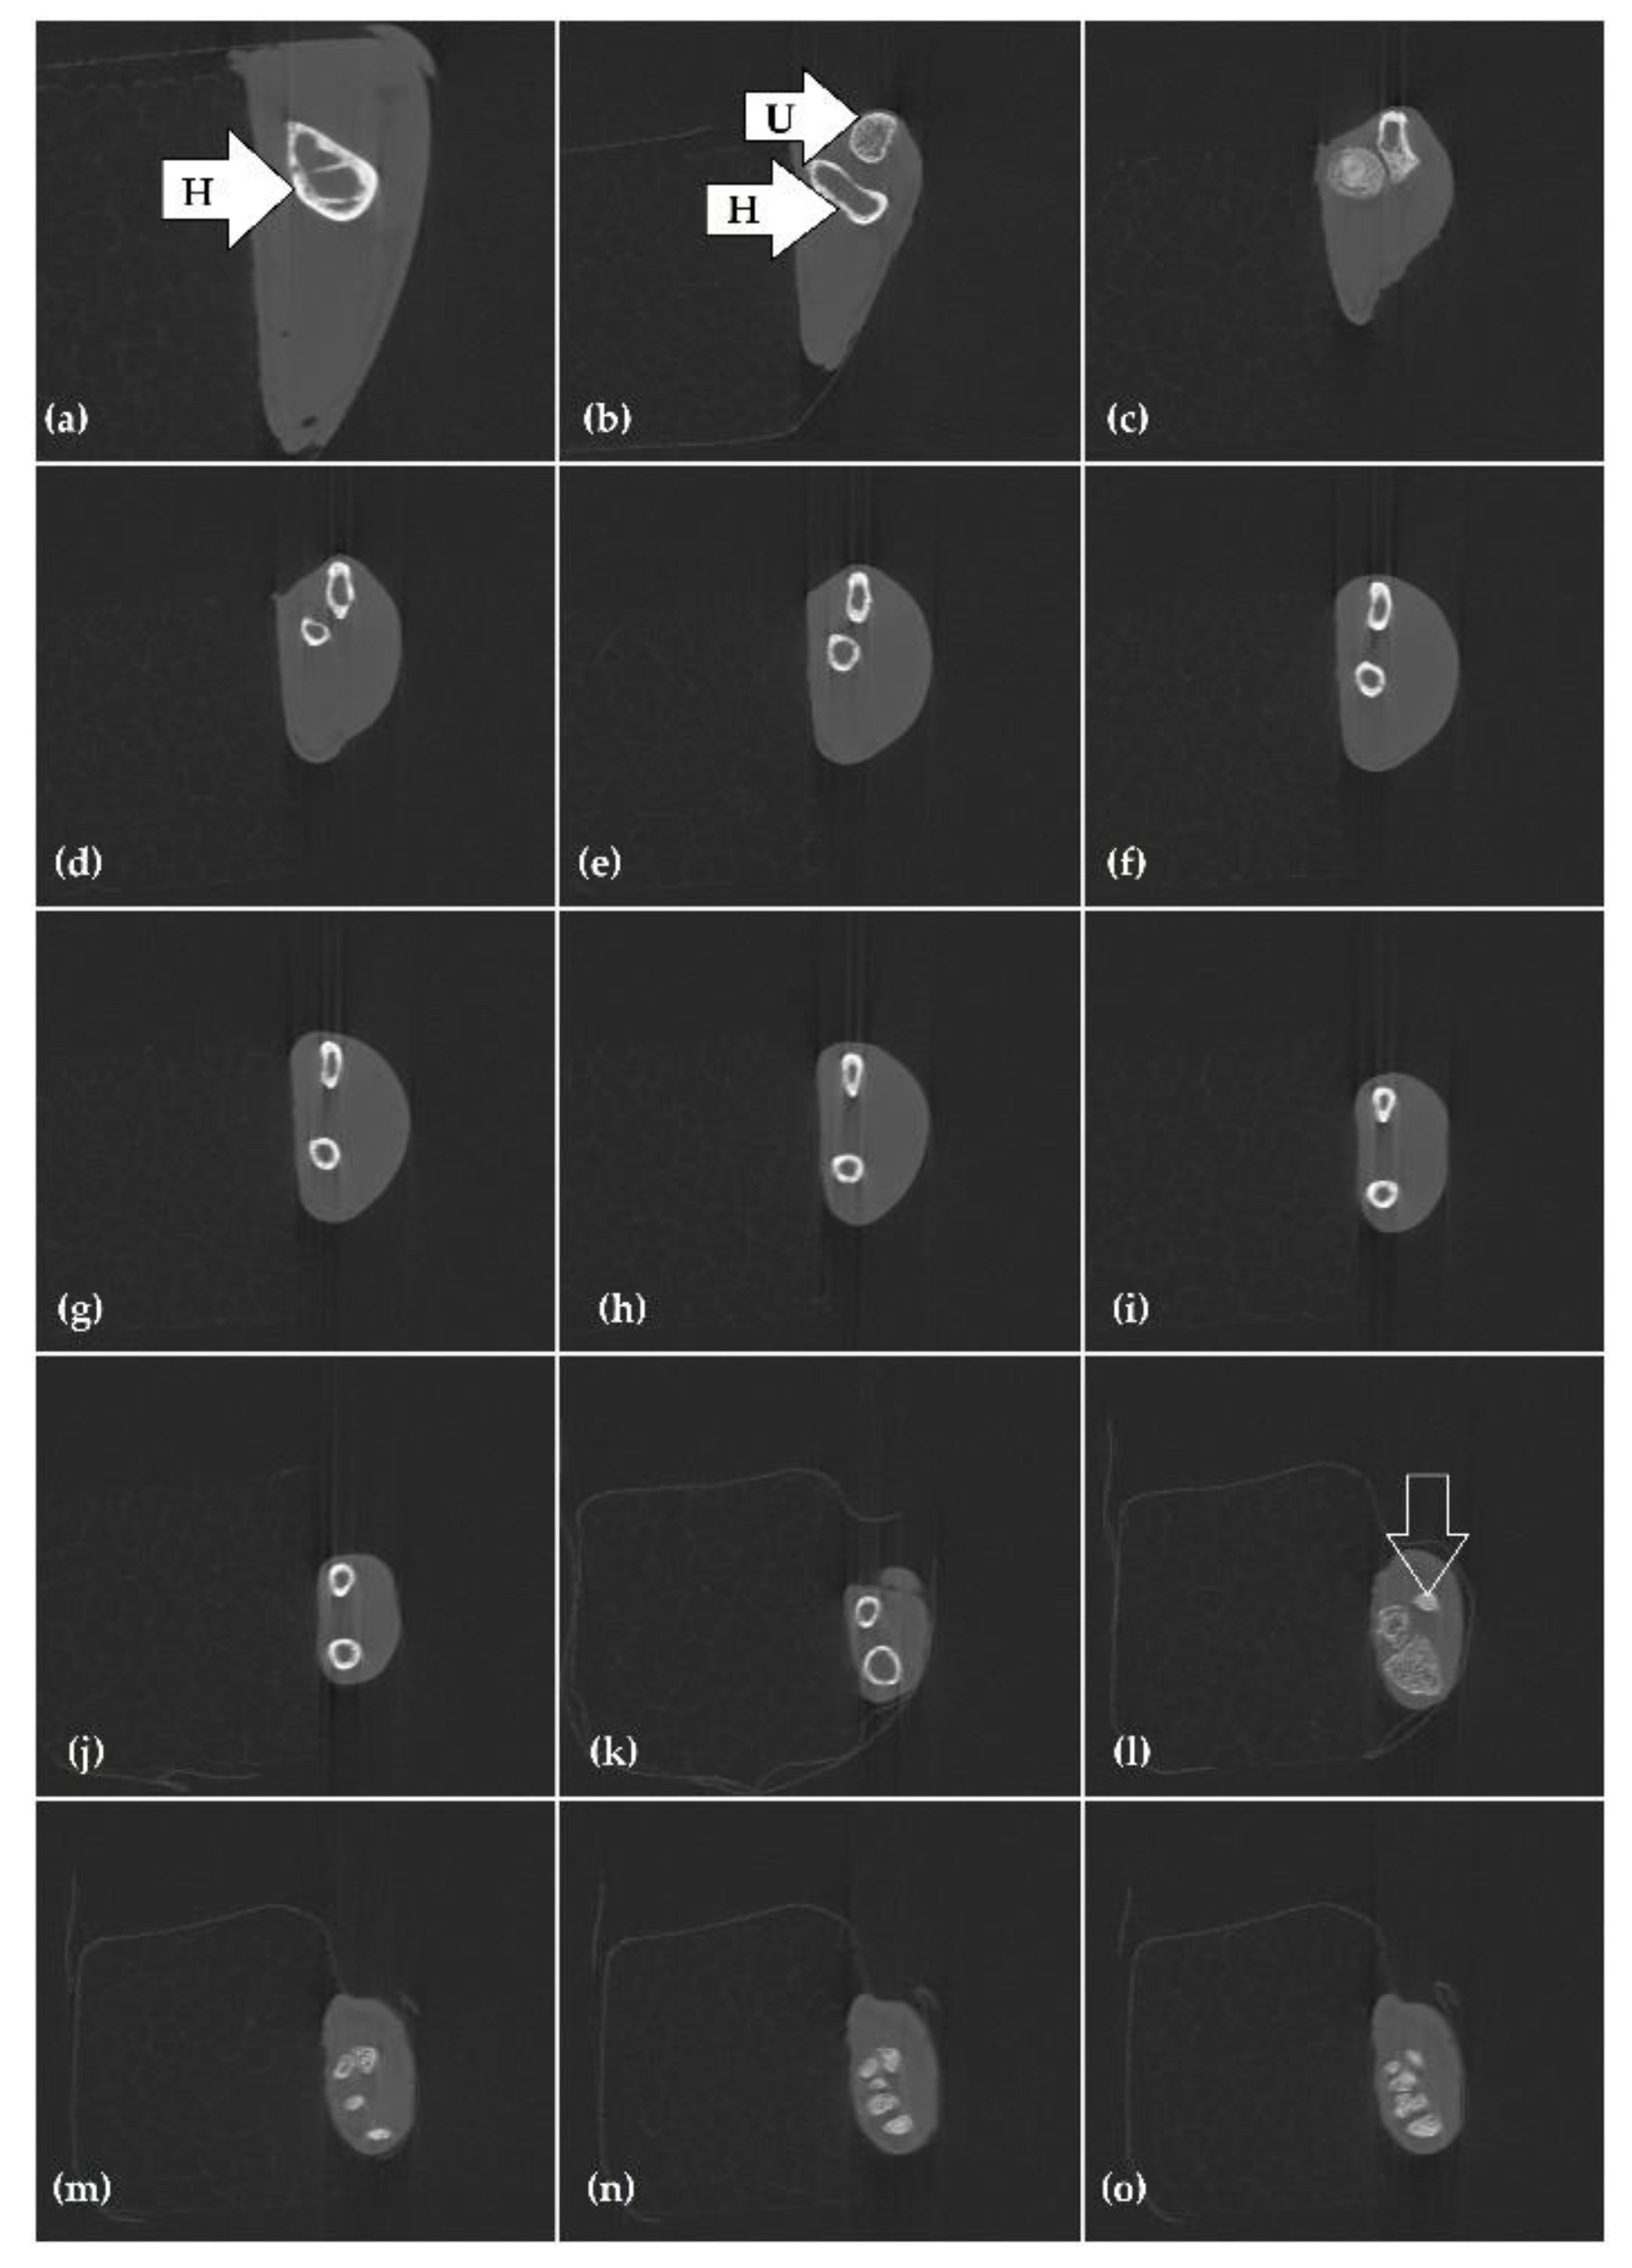

3.3. Microcomputed Tomography Examination (Micro-CT)